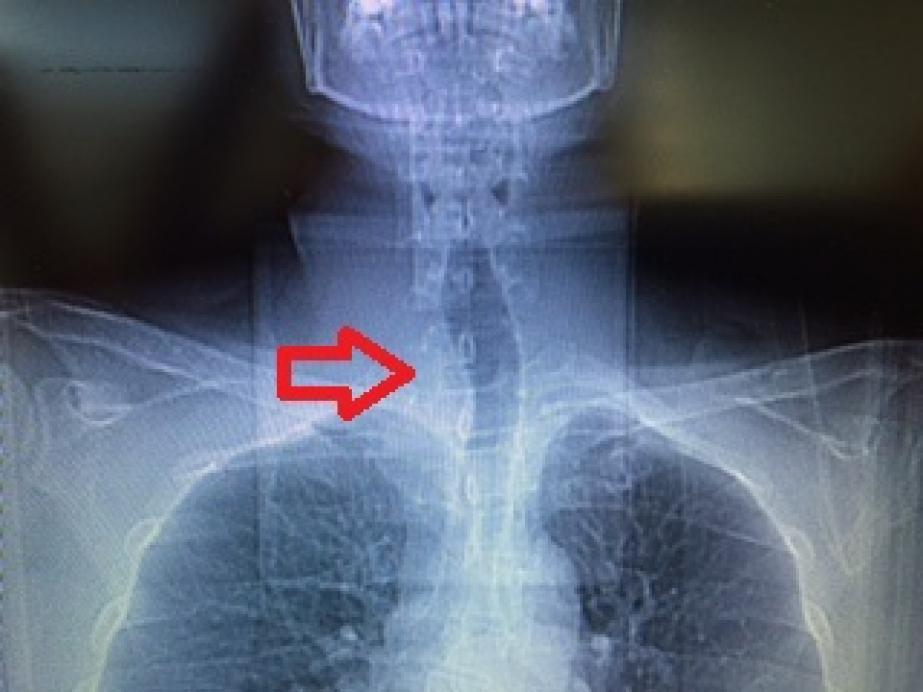

- Bu belirtiler sizde varsa tiroid hastalığınız olabilir !!

- Hipotiroidi Belirtileri

- Hipertiroidi Belirtileri

- Tiroid iltihabı (Hashimoto)